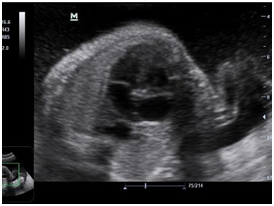

Newborn female was born at 37 weeks 5 days as a product of a second pregnancy, with prenatal diagnosis of duodenal atresia and esophageal stenosis (Figure 1). Due to a previous cesarean section and rupture of the membranes, an emergency caesarean section was performed. Birth weight was 2100 grams APGAR scores were 8–9 at…min. A thoracic-abdominal radiograph was performed, showing thorax without alterations and an image suggestive of duodenal atresia (Figure 2). An echocardiogram CIA 0.5, PCA: 0.2X0.3 showed mild dysplasia of aortic and pulmonary valves. Abdominal laparotomy at 24hours of life, revealed duodenal stenosis secondary to annular pancreas, intestinal malrotation and non-meconium plastic peritonitis without evidence of perforation. The defect was corrected by adhesiolysis, duodeno-duodenal anastomosis and incidental appendectomy.

Figure 1 Prenatal ultrasound: A) image of the double bubble suggestive of atresia/duodenal stenosis (stomach to the left and more centered the duodenum). B) Behind the heart, hyopecogenic image that corresponds to the dilated esophaguss.